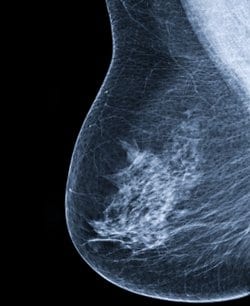

לנשאיות למוטציות BRCA סיכון מצטבר של 70% ללקות בסרטן השד עד הגיען לגיל 80, אלו מסקנותיו של מחקר חדש שפורסם בכתב העת JAMA.

במסגרת המחקר נערך מעקב אחר כ- 10,000 נשים עם המוטציות BRCA1 ו- BRCA2 . לאורך חציון של חמש שנים, הסיכון המצטבר לסרטן השד עד גיל 80 היה 72% בקרב נשאיות ל- BRCA1 ו- 69% בקרב נשאיות ל- BRCA2 . הסיכון המצטבר לתחלואה בסרטן השחלות היה 44% בקרב הנשאיות ל- BRCA1 ו- 17% בקרב הנשאיות ל- BRCA2.

הסיכון המצטבר לסרטן בשד הנגדי, 20 שנה לאחר סרטן שד ראשון, היה 40% בקרב הנשאיות ל- BRCA1 ו- 26% בקרב הנשאיות ל- BRCA2 . עבור כל הנשאיות, הסיכון לסרטן השד עלה ככול שגדל מספר הקרובות מדרגה ראשונה ושנייה אשר חלו בסרטן השד. מנגד, הסיכון לסרטן השחלות לא הושפע מההיסטוריה המשפחתית.